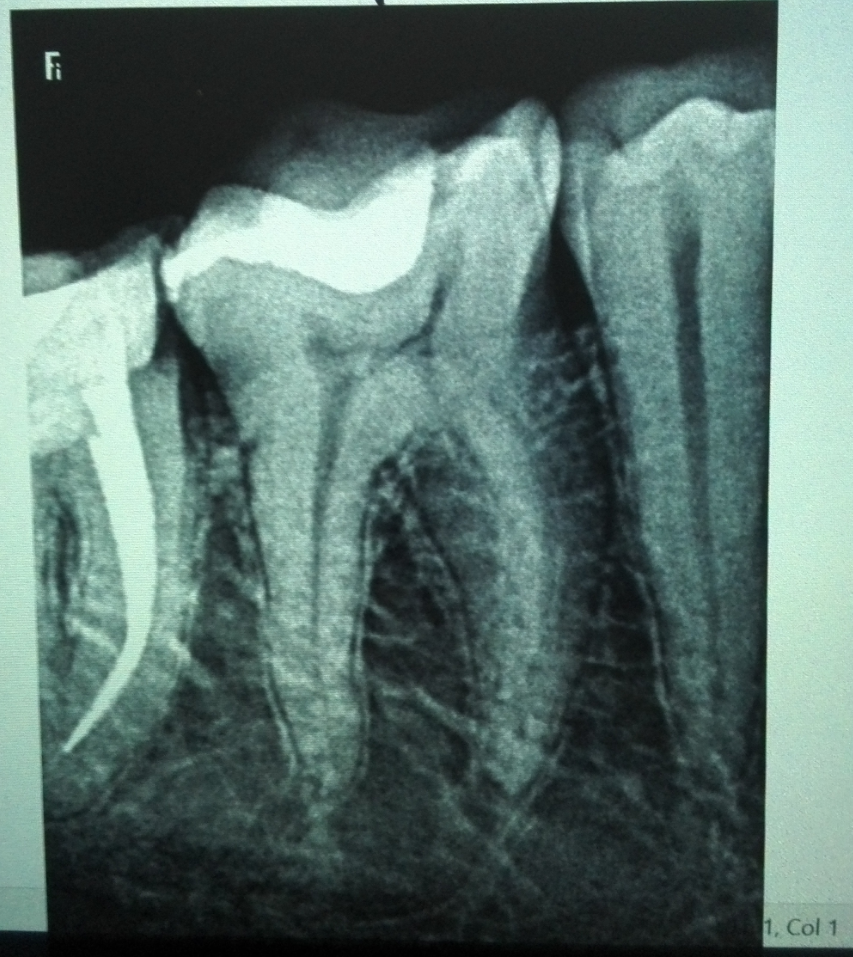

на втором фото, обозначены "подозрительные" места,  похоже ли это на кариес ?

Original-2020-08-20-080751.png

edited-2020-08-20-080751.png